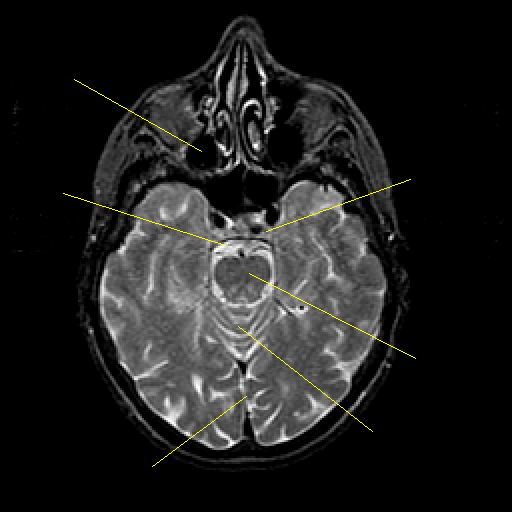

T2-weighted structural MR: Slice 19

Slice 19

Pointers

Labeled